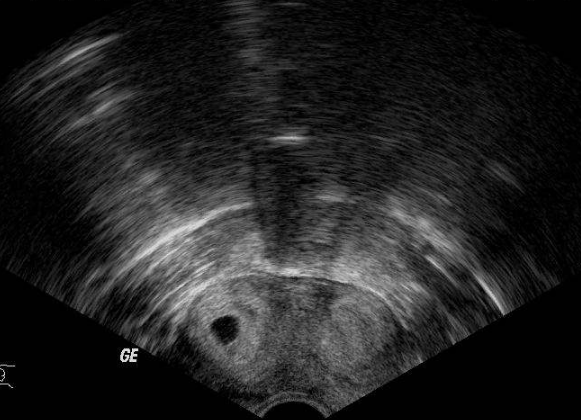

雙角子宮圖片

雙角子宮 (7)